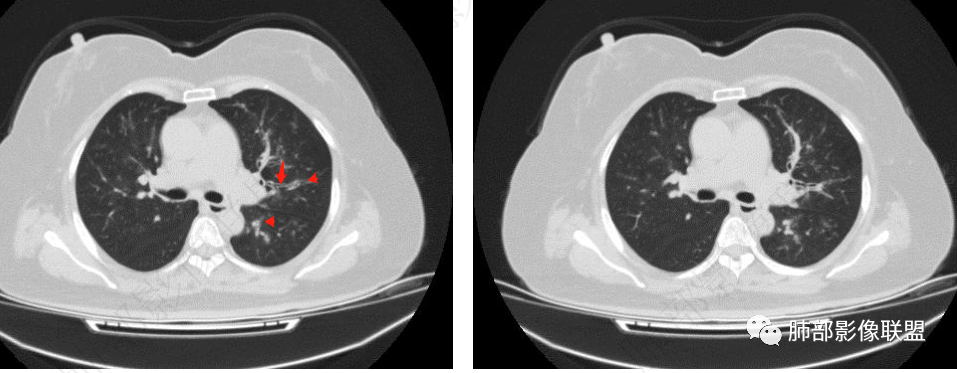

1.病灶沿支气管分布的特点相当明显,相应支气管壁广泛增厚。这种与支气管关系极为密切的片影和/或结节影,常高度提示气道相关感染,如支气管肺炎。

2.患者两肺多发病变,具有广泛性。如此广泛分布更多见于免疫低下的机会性感染。

3.支气管壁广泛增厚对气道侵袭性曲霉病具有一定的提示意义。注意患者没有支气管扩张,临床也未提供IGE等实验室资料。

4.老年女性患者,咳嗽少痰,伴喘息气短8天。注意患者没有发热,中毒症状不明显。既往糖尿病、高血压病史。

炎性指标升高,头孢等药物覆盖疗效不佳。

1.器官支气管管套样壁增厚和/或支气管扩张,注意壁增厚较均匀,和/或伴有播散性小片影及结节影,注意这些小片影或结节影边界有时较普通炎性病灶清楚。

2.可以阻塞支气管造成肺不张而酷似中央型肺癌。偶而可呈大范围毛玻璃样影。